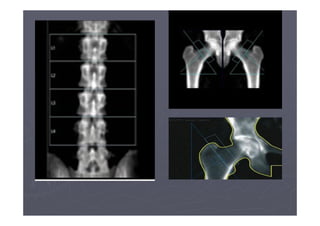

OSTEOPOROSE

PROCEDIMENTO

Definição da OMS

► T-score -1 a –2.5 = osteopenia

► T-score menor que –2.5 = osteoporose

► Presença de fragilidade indica osteoporose

severa

►DMO – DENSIDADE MINERAL ÓSSEA

►Z-score – DADOS OBTIDOS NO BANCO DE

DADOS PARA ANÁLISE COMPARATIVA.